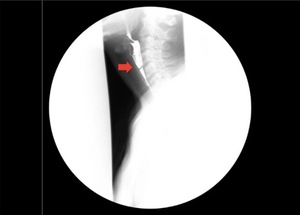

Based on the patient’s presenting symptoms, a barium swallow (i.e., upper gastrointestinal tract x-ray exam) was obtained, which demonstrated an incomplete cricopharyngeal web (i.e., mucosal web that tethers the lateral hypopharyngeal wall to the cricopharyngeus muscle) (red arrow in Figure 1), extending from the anterior wall at the level of C5-C6 with barium passing through the web without appreciable delay.